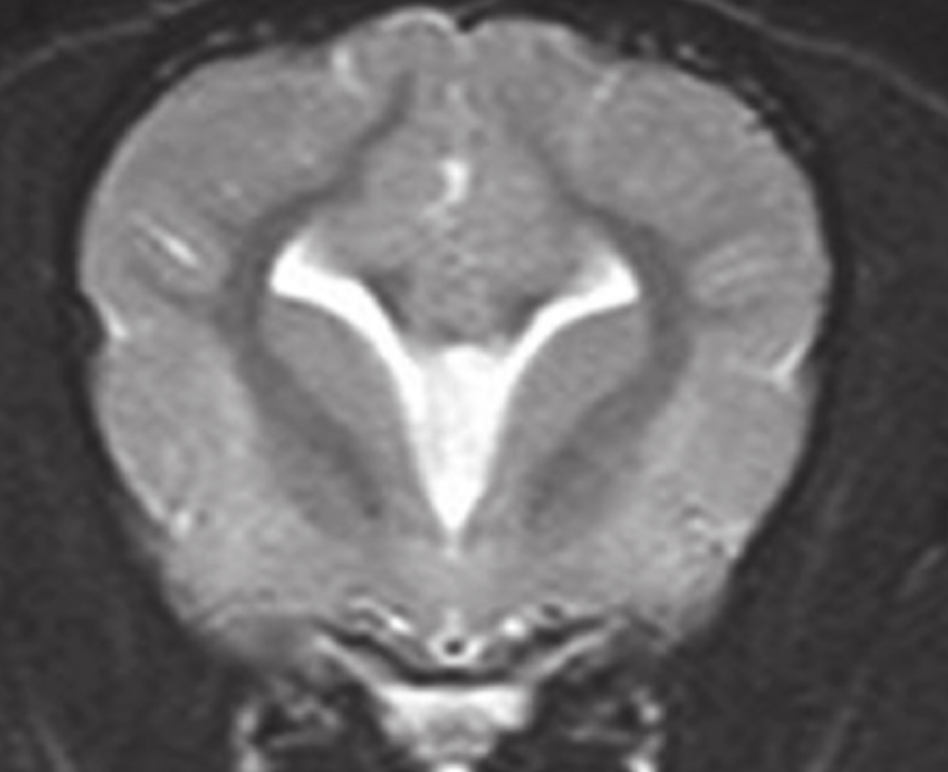

This appearance of the lateral ventricles is often associated with what condition?

Associated with complete or partial corpus callosal aplasia

“Upturned, pointed dorsal corners of lateral ventricles; bat-wing appearance”